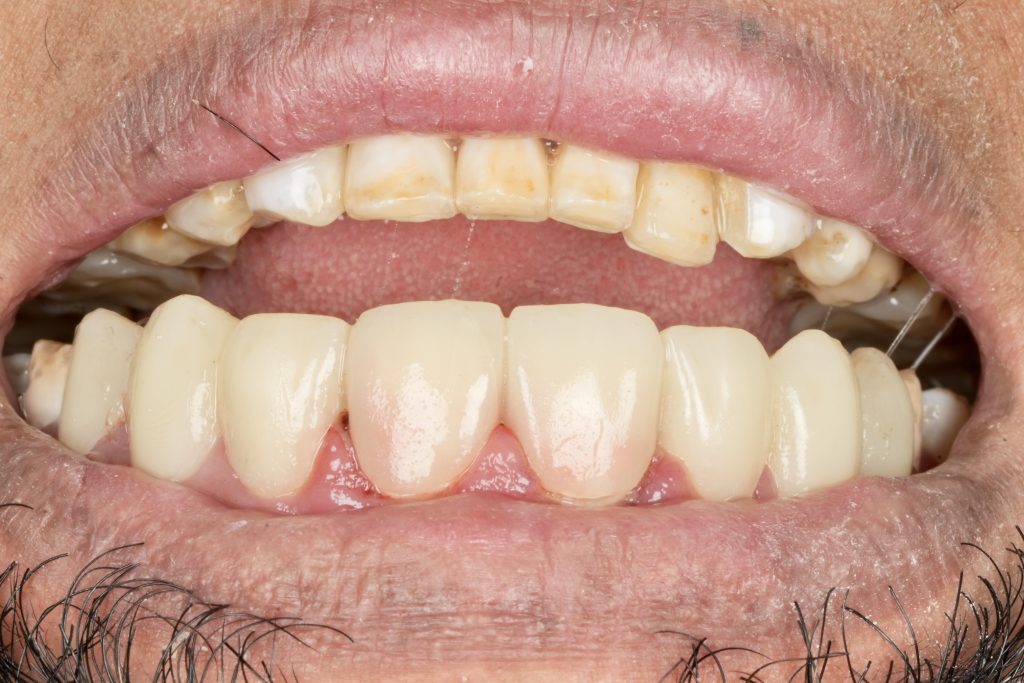

5️⃣ Adhesive Protocol and Bonding

Each veneer was etched with 9 % HF acid for 20 seconds, silanated, and dried. Teeth were treated with 37 % phosphoric acid and universal adhesive (Clearfil Universal Bond Quick). Light-cure resin cement (Variolink Esthetic LC) was applied under full-arch rubber-dam isolation. Excess cement was removed and polymerization performed for 40 s per surface (Fig 4).